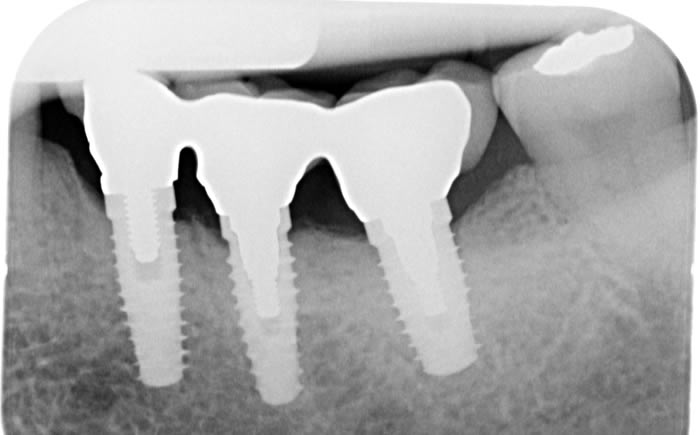

Case One (3 images)

Missing lower teeth replaced by three dental implants and crowns.